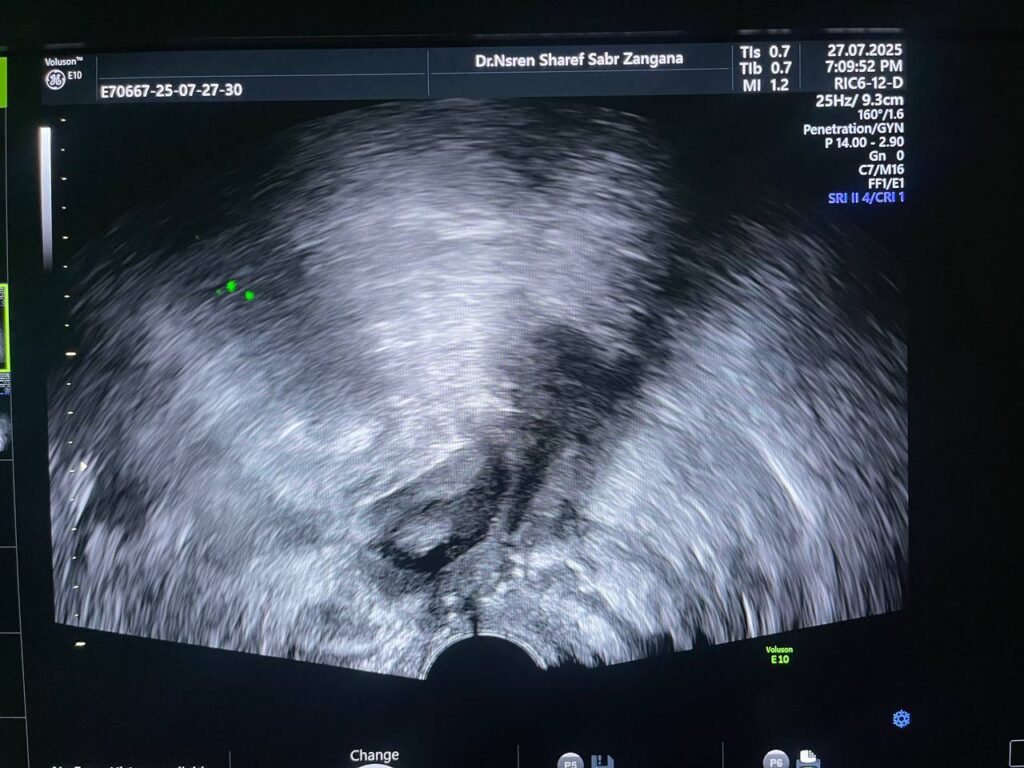

Post Hystercetomy Abcess Formation

Uterus removed , with presence of collected heterogenous fluid 27x14mm in the bed , contain air , could be abscess ? please for further study to exclude other pathology